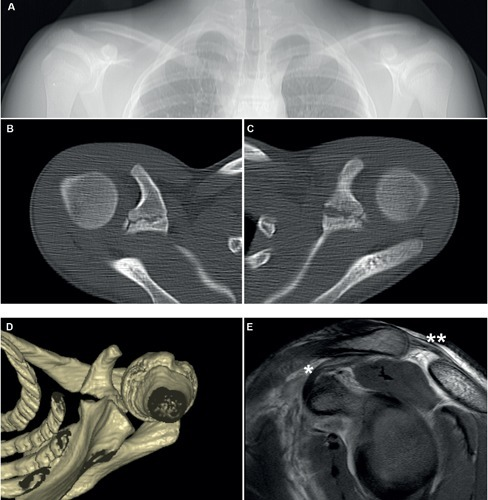

Clinical image for Acromioclavicular Joint Injury

What is your clinical and radiological assessment of AC joint injuries? How do you differentiate grades?